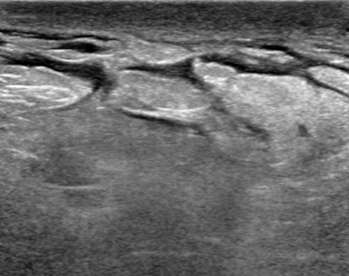

Sonographic architectural distortion

The ultrasound image above demonstrates sonographic architectural distortion. The hyperechoic (bright) bands of tissue interdigitating between the fat in the breast become focally altered and seem to radiate around a small lesion. Biopsy revealed a complex sclerosing lesion (sometimes called a radial scar) which is a benign, but sometimes high risk lesion, which can be recognized as architectural distortion on ultrasound. Other examples of benign causes of architectural distortion include sclerosing adenosis, fat necrosis, post-procedural changes, granular cell tumors, and breast fibromatosis. Architectural distortion may also be associated with breast cancer, as evidenced by the example below: